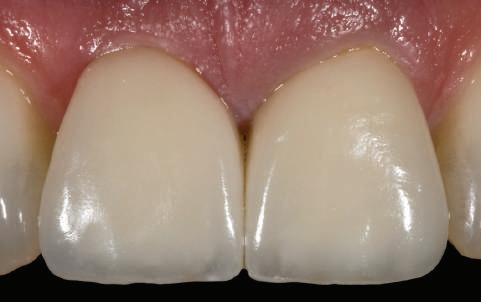

Influenţa pozitivă a contururilor coronare asupra esteticii ţesuturilor moi

50